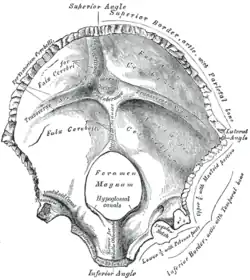

Occipital bone at birth, seen from below. (Squamous part is top half, portion above foramen magnum, shown in yellow.) | |

The internal surface is deeply concave and divided into four fossae by the cruciform eminence.

The upper two fossae are triangular and lodge the occipital lobes of the cerebrum; the lower two are quadrilateral and accommodate the hemispheres of the cerebellum.

At the point of intersection of the four divisions of the cruciform eminence is the internal occipital protuberance.

From this protuberance the upper division of the cruciform eminence runs to the superior angle of the bone, and on one side of it (generally the right) is a deep groove, the sagittal sulcus, which lodges the hinder part of the superior sagittal sinus. To the margins of this sulcus the falx cerebri is attached.

The lower division of the cruciform eminence is prominent and is named the internal occipital crest; it bifurcates near the foramen magnum and gives attachment to the falx cerebelli. In the attached margin of this falx is the occipital sinus, which is sometimes duplicated.

In the upper part of the internal occipital crest, a small depression is sometimes distinguishable; it is termed the vermian fossa since it is occupied by part of the vermis of the cerebellum. Transverse grooves, one on either side, extend from the internal occipital protuberance to the lateral angles of the bone; those grooves accommodate the transverse sinuses, and their prominent margins give attachment to the tentorium cerebelli.

The groove on the right side is usually larger than that on the left and is continuous with that for the superior sagittal sinus.

Exceptions to this condition are, however, not infrequent: the left may be larger than the right or the two may be almost equal in size.

The angle of union of the superior sagittal and transverse sinuses is named the confluence of the sinuses, and its position is indicated by a depression situated on one or other side of the protuberance.